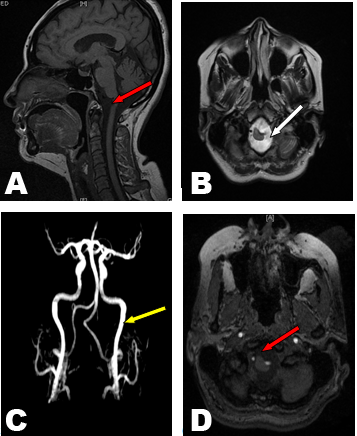

Images show anomalous left vertebral artery impressing into the cord substance at cervico–medullary junction causes cervico-medullary stenosis, no evidence of cerebral tonsil herniation or syrinx formation, in right parietal sub cortical white matter; two small high signal intensity foci were seen on T2 and FLAIR images suggestive of ischemic foci. Brain MRA confirmed malformation in the left vertebral artery, images of MRA showed the left vertebral artery entering foramen magna with medial tortuous kinking to the medulla oblongata.

Normal MRI scan appearance of the basal ganglia, thalami, internal and external capsule on both sides were detected also the ventricular system and extra axial cerebrospinal fluid (CSF) space are within normal limits, no mass effect or midline shift. Normal configuration of optic chiasm, optic nerves, pituitary gland and its stalk, Normal features of the cerebellar hemispheres, vermis, peduncles and brain stem with no abnormal intensities. Normal MRI features of the cerebello pontine angles and internal auditory canal, no evidence of space occupied lesion (SOL), fresh or sub dural collection was detected. (Figure 1)

Figure 1: (A) Magnetic resonance imaging sagittal T1 showing spinal cord cervico medullary stenosis (red arrow) due to anomalous vertebral artery, (B) Axial T2 showing cervico medullary sub arachnoid space enlargement, (C) MRA showing kinking left vertebral artery (yellow arrow), (D) Time of flight axial image showing the anomalous vertebral artery (red arrow).